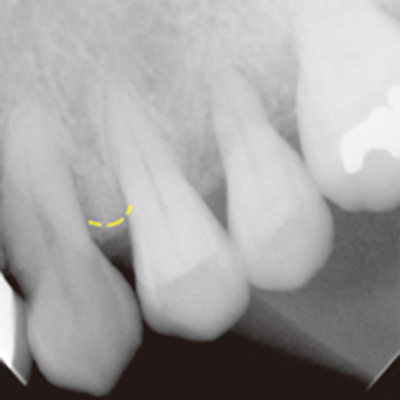

案例1

補骨前

補骨後